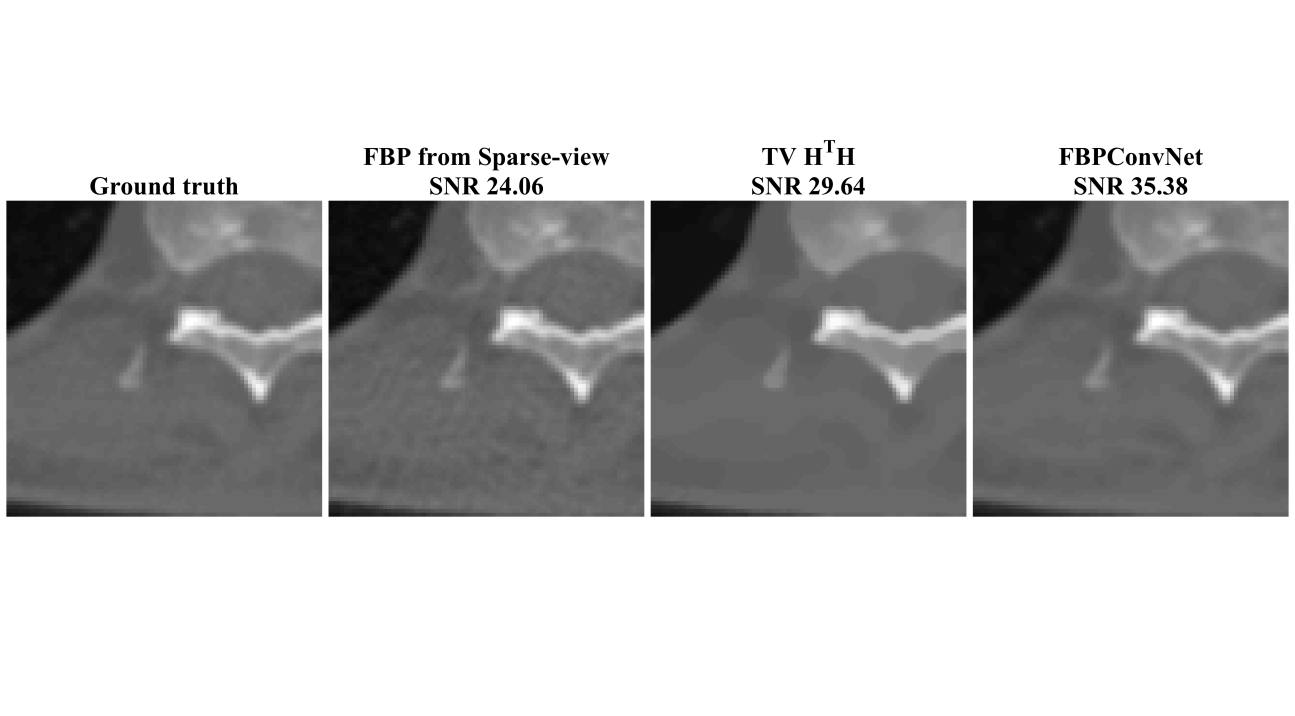

Figures 5 and 6 and Table II show the results for the biomedical dataset. In Figure 5, again, the sparse-view FBP contains line artifacts. Both TV and the proposed method remove streaking artifacts satisfactorily; however, the TV reconstruction shows the cartoon-like artifacts that are typical of TV reconstructions. This trend is also observed in severe case (x20) in Fig. 6. Quantitatively, the proposed method outperforms the TV method.

| avg. SNR (dB) | 143 views (x7) | 24.97 | 31.92 | 36.15 |

| 50 views (x20) | 13.52 | 25.2 | 28.83 | |